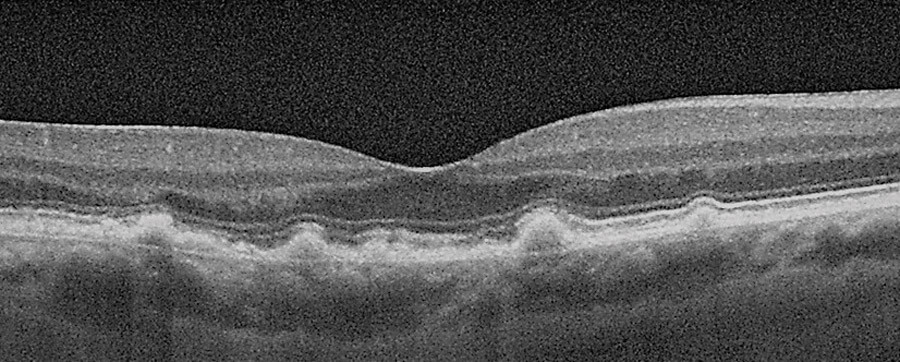

Figure 4: OCT scan of Drusen.

Drusen and other deposits: Are a lipoprotein type extracellular deposit that is deposited under the RPE. They can be classified by their size as:

- Small (drupelets): X< 63 microns

- Intermediate: X≥ 63 microns and X ≤125 microns

- Large: X> 125 microns.

Differently we can find: subretinal drusenoid deposits (know as pseudo-drusen) traceable above the RPE and a further type of drusenoid deposit, called cuticular drusen, located between the basal lamina of the RPE and the inner collagenous layer of Bruch’s membrane.